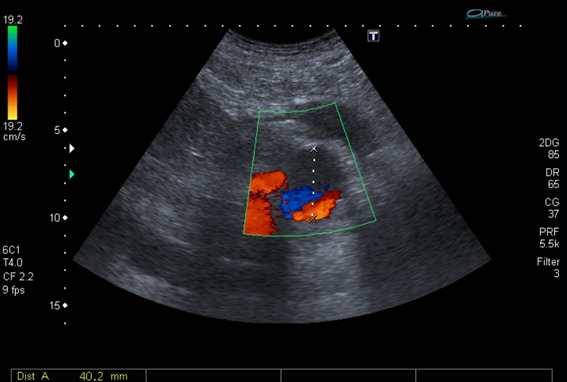

A 69-year-old man underwent liver transplantation with a deceased donor for cirrhosis secondary to steatohepatitis. The arterial anastomosis was performed between the celiac trunk of the donor and the hepatic artery of the recipient. In the second postoperative month, he developed abdominal pain and abnormal liver function tests. MRI angiography and subsequent digital angiography confirmed a 50 x 60 mm hepatic artery pseudoaneurysm (PAH) with dilation of the bile duct and bilomas in both hepatic lobes. Endovascular treatment could not be performed due to the absence of contrast passage to the intrahepatic branches during angiography. A surgical ligation and resection of the PAH that compromised both hepatic arteries was chosen. The primary anastomosis was not viable because it was not possible to identify a viable proximal end or ostium. Given the ischemic compromise of the bile duct, an exception route for re-transplantation was requested from INCUCAI, thus entering the waiting list and accessing a new graft 30 days later. His subsequent evolution was favorable. Now he's asymptomatic under follow-up after 9 years of the liver re-transplantation.